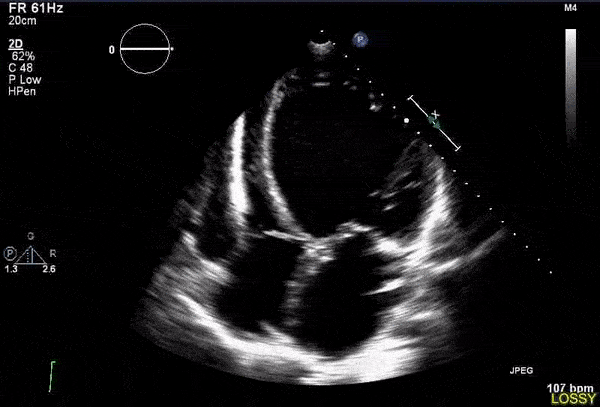

·超声心动图 , 用来测量心脏结构和功能;

文章插图

运动员组具有更高的左心室重量(左心室心肌肥厚 , 是一种适应性变化)和舒张末期容积更大(说明心脏泵血功能更强大) , 而静息状态下心功能没有差异 。